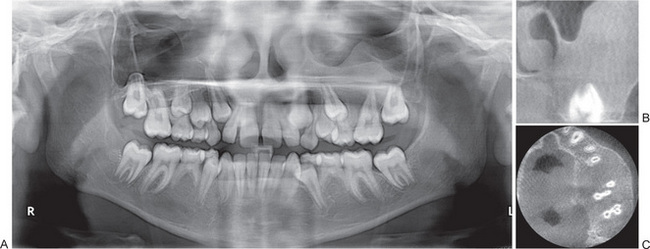

Radiographic features are usually diagnostic. Because the disease is a heterogeneous group of disorders, the findings vary depending on the subtype. Patients usually have generalized osteosclerosis. Bones may be uniformly sclerotic, but alternating sclerotic and lucent bands may be noted near the ends of long bones (Fig. 17-6). The bones might appear club like or show an appearance of a bone within bone (endobone). The entire skull is thickened and dense, especially at the base. Sinuses are small and underpneumatized. Vertebrae are extremely radiodense. They may show alternating bands, known as the ‘rugger-jersey’ sign. Radiographs may show evidence of fractures or osteomyelitis. When the jaws are affected, the density of the bone may be such that the roots of the teeth are nearly invisible on the dental radiograph.

Bone biopsy is not essential for diagnosis because radiographs are usually diagnostic. Osteopetrosis is characterized by the endosteal production of bone with an apparent concomitant lack of physiologic bone resorption (Fig. 17-7). Osteoblasts are prominent, but osteoclasts are seldom found in significant numbers in tissue sections. The predominance of bone formation over resorption typically leads to the persistence of cartilaginous cores of bony trabeculae long after their replacement should have occurred in endochondral bones. The trabeculae themselves are disorderly in arrangement, and the marrow tissue present is usually fibrous.

Figure 17-7 Osteopetrosis.

A photomicrograph of a long bone showing replacement of the marrow by endosteal bone. (Courtesy of Dr Frank Vellios)